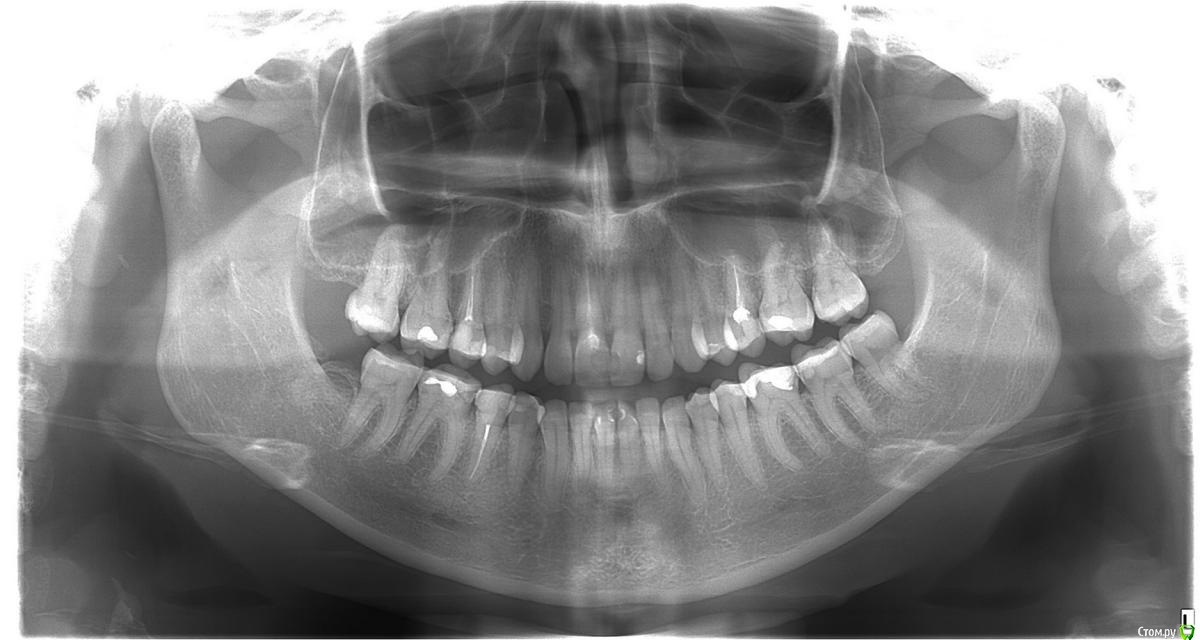

Леся181 Опубликовано 29 сентября, 2020 Поделиться Опубликовано 29 сентября, 2020 Добрый день!Хочу поменять старые пломбы на вкладки на 36-37 зубы. На консультации врач сказала, что нужно в 36 удалять нерв, так как пломба слишком большая и глубокая. Близко к нерву и есть вероятность что после установки, зуб может заболеть. Посоветуйте, стоит ли удалять нерв? Или искать другого доктора? Ссылка на комментарий

kramer Опубликовано 29 сентября, 2020 Поделиться Опубликовано 29 сентября, 2020 Удалять нерв в том случае, если есть сообщение кариозной полости с нервом (судя по снимку вероятность этого высокая) 1 Ссылка на комментарий

АнтонТЛТ Опубликовано 29 сентября, 2020 Поделиться Опубликовано 29 сентября, 2020 На 37 зубе тоже глубокая кариозная полость под пломбой. Ссылка на комментарий